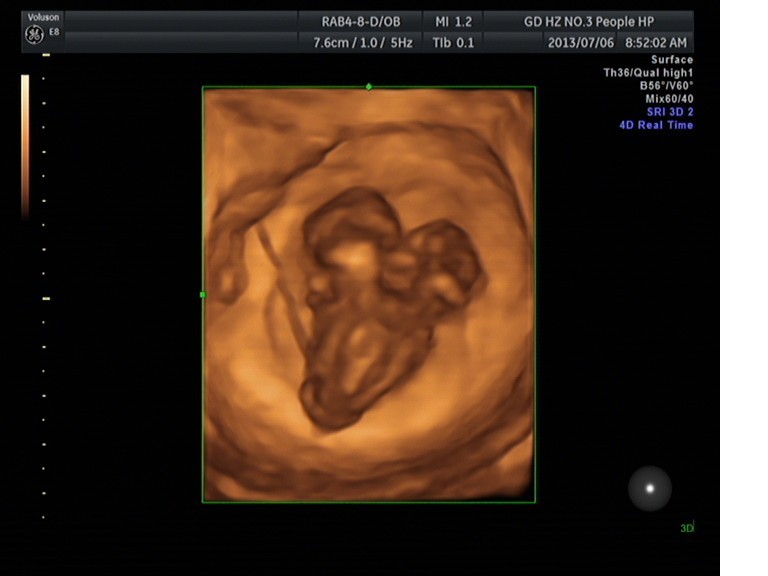

隨著環(huán)境污染日益嚴(yán)重,隨著各種地溝油的誕生,隨著各樣鎘大米的泛濫……我們的健康越來(lái)越受到威脅,很多疾病也隨之接踵而至,胎兒先天性疾病也越來(lái)越多見(jiàn)。7月6日,我院超聲科王瑤醫(yī)生在做胎兒產(chǎn)前NT篩查中發(fā)現(xiàn)一例孕約11周+的聯(lián)體雙胎。超聲所見(jiàn):增大的子宮內(nèi)可見(jiàn)聯(lián)體雙胎兒回聲,可見(jiàn)兩個(gè)胎頭不能分離,胸部及腹部融合,可見(jiàn)一個(gè)增大的心臟。

聯(lián)體嬰兒B超圖像